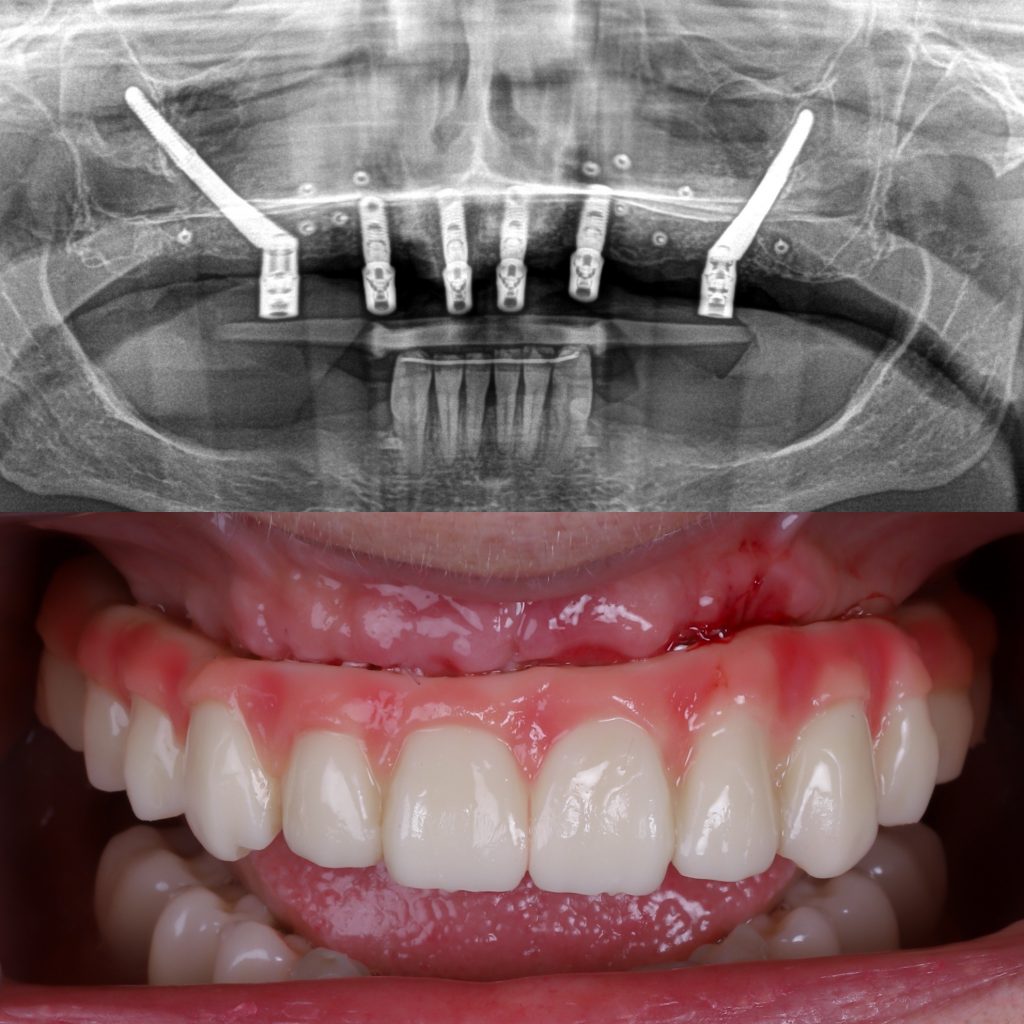

Los implantes cigomáticos son un tipo de implante dental especialmente diseñado para pacientes que no tienen suficiente hueso en el maxilar superior. A diferencia de un implante convencional, que se fija en el hueso del maxilar, el implante cigomático es más largo y se ancla en el hueso cigomático (el pómulo), una zona muy densa y estable que siempre mantiene suficiente estructura ósea, incluso cuando el maxilar está muy reabsorbido.

El número de implantes cigomáticos necesarios suele variar entre 1 y 4 por arcada y depende principalmente de la calidad del hueso maxilar y la calidad del hueso cigomático (pómulo). Cuando el hueso del maxilar no es suficiente, utilizamos el hueso cigomático (el pómulo) como punto de anclaje.

Sin embargo, cuando no existe buen hueso maxilar en ninguna zona, o incluso cuando el punto de apoyo en el pómulo no ofrece la estabilidad ideal, pueden necesitarse hasta 4 implantes cigomáticos para conseguir una fijación segura y permitir una rehabilitación fija inmediata.

Un implante cigomático mide entre 35 mm y 55 mm, mucho más que un implante dental convencional, que suele medir entre 8 y 18 mm. Su longitud permite alcanzar el hueso del pómulo para ofrecer la estabilidad necesaria en casos de atrofia ósea severa.